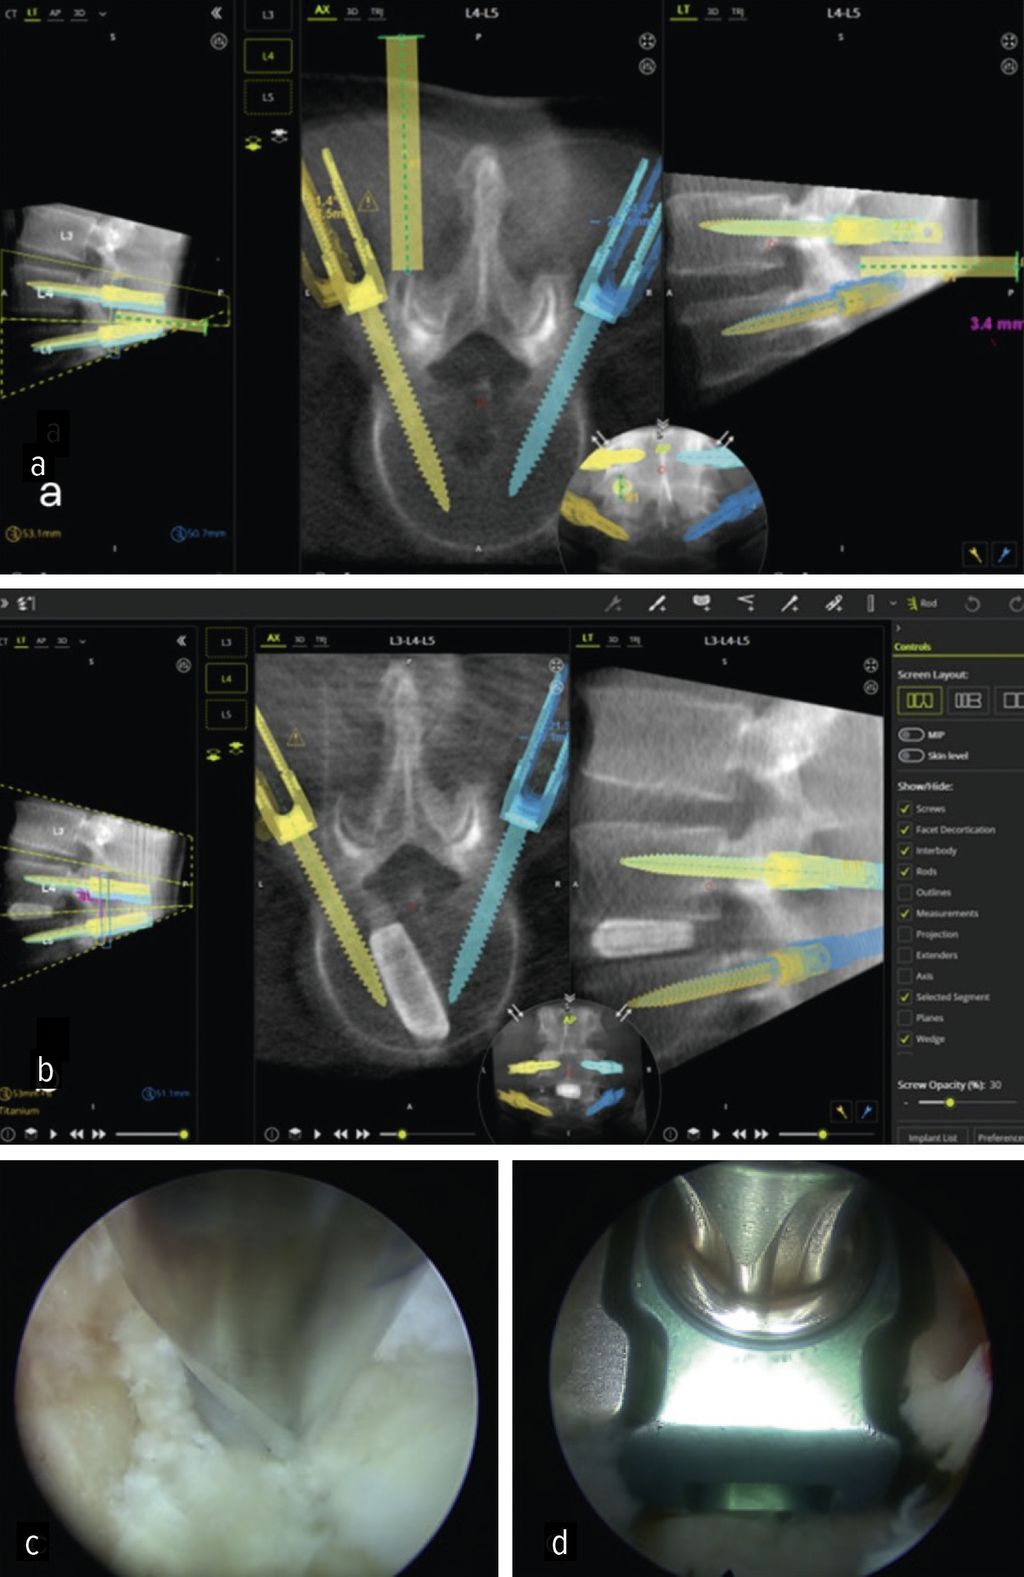

Lumbale interkorporelle Fusion

Die minimalinvasive transforaminale lumbale interkorporelle Fusion (Minimally Invasive Transforaminal Lumbar Interbody Fusion; MIS-TLIF) hat in den letzten Jahren an Bedeutung gewonnen, die aufgrund des geringeren Gewebetraumas mit einer früheren Rekonvaleszenz verbunden ist.24 Aus den gleichen Gründen rückt die endoskopische transforaminäre Interbody Fusion (Endo-TLIF) in den Fokus der Aufmerksamkeit. Endo-TLIF ist eine Erweiterung der MIS-TLIF und erfordert eine unilaterale Resektion des Facettengelenkes. Die Grund- und Deckplattenpräparation gilt als entscheidender Faktor, der die Fusionsrate beeinflusst.24 Die Möglichkeit, unter klarer endoskopischer Sicht die Endplatten präzise darzustellen, erlaubt eine ideale Aufbereitung des Fusionsbettes. Dies könnte zu einer Erhöhung der Fusionsrate beitragen. Zudem profitieren die Patienten durch eine raschere Erholung, einen geringeren Opioidbedarf, eine frühzeitige Mobilisierung und eine verkürzte stationäre Verweildauer.25 Limitationen liegen aktuell bei höhergradigen Listhesen und kollabierten Bandscheibenräumen vor.26 Um das Potenzial der Methodik zu untermauern, bedarf es robuster Studien mit erhöhtem Evidenzlevel sowie eines einheitlichen Standards der endoskopischen Fusionstechniken. Abbildung 6 zeigt eine Planungsanwendung (MazorX® Application, Fa. Medtronic) für Endoskoptrajektorie und Pedikelschraubenimplantation im Rahmen der Endo-TLIF-Operation (a, b). Abbildung b zeigt einen oblique eingebrachten Cage (eFuse® expandable, Fa. Evospine), Abbildung c einen Nukleusresektor (Fa. RIWOspine) bei Präparation des Fusionsbettes. Abbildung d zeigt, dass eine Cagedistraktion unter direkter Sicht möglich ist.

Höhere Genauigkeit, kürzere Krankenhausaufenthalte und geringere Strahlenexposition sind die Gründe für den Einsatz bei der Pedikelschrauben-Implantation.32 Zusätzlich bieten sie den Vorteil der exakten physischen Führung, um präoperativ geplante chirurgische Trajektorien in der Endoskoppositionierung umzusetzen. Wang et al. setzten robotische Assistenz bei vollendoskopischen lumbalen Diskektomien ein und konnten Sicherheit und Effektivität als Alternative zur konventionell fluoroskopischen ESS bestätigen.38 Im eigenen Haus wurde das Verfahren bei der endoskopischen TLIF-Operation angewandt.